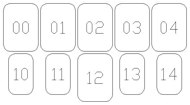

- OO-1. Intra-oral Full Mouth Series Structured Display